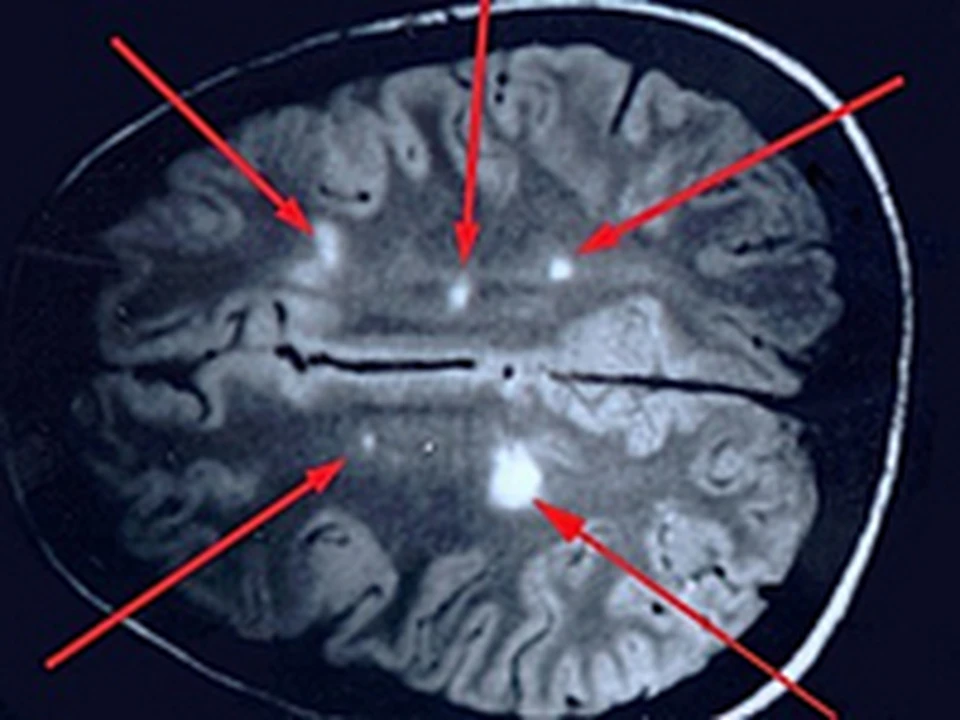

Иллюстрации и пояснения: гиподенсивный очаг на КТ головного мозга